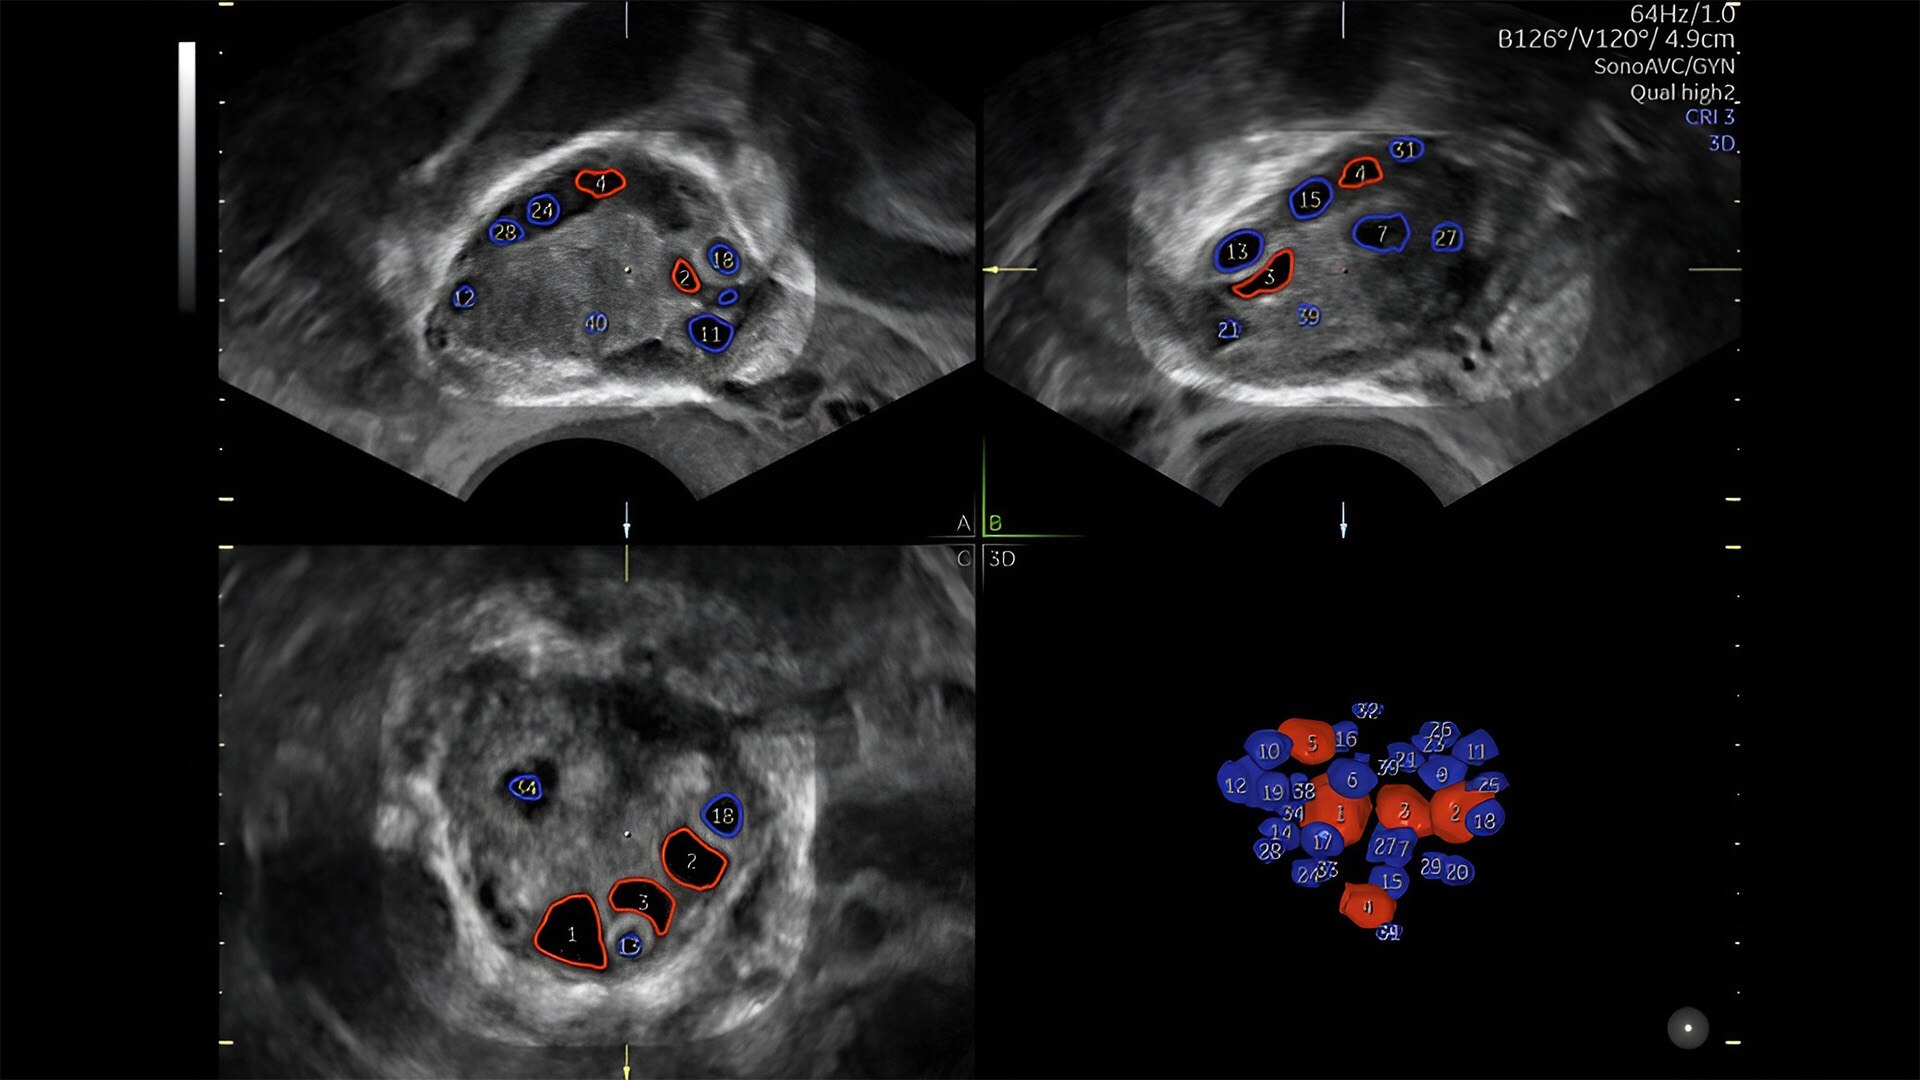

Pelvic health

Offer patient answers faster with Ai-based automation tools